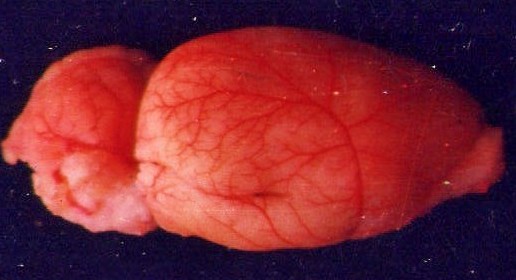

My research led to an innovative experiment. To visualize cerebral circulation in rats, we injected a special red dye directly into the left ventricle of the heart while it was still beating. The heart's own natural pumping force then distributed the dye throughout the bloodstream, including to the brain. This method allowed us to map brain circulation accurately, avoiding the potential artifacts of manual perfusion.

The rat's normal brain circulation